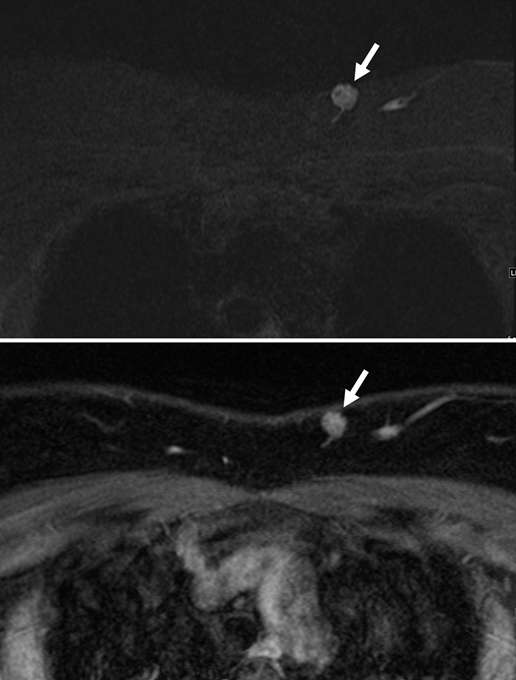

Figure 4B. Arteriovenous malformation. Pre-contrast T2-weighted inversion recovery (top) and post-contrast T2-weighted fat saturation (bottom) sequences of the chest in the same patient demonstrate an avidly enhancing high-flow vascular lesion (arrows). A feeding vessel supplying the lesion can be seen inferiorly as a linear hyperintensity, and an outflow vessel can be seen as a dilated vein laterally adjacent to the lesion. The diagnosis was consistent with an arteriovenous malformation.